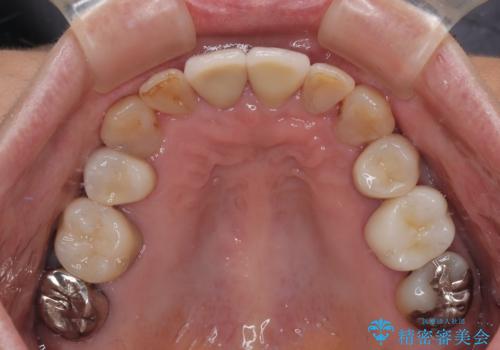

- 長年気にしていた捻れた前歯が欠けたとのことで来院された患者様です。

矯正治療に抵抗があったそうですが、前歯が欠けたことをきっかけに、矯正治療で歯列を整えた上で、セラミッククラウン治療を行う決心が付いたとのことでした。

デコボコが強いため、ブリッジや残根となっている部分のスペースを利用して歯列を整え、変色や欠けている歯をオールセラミッククラウンによる補綴治療を行うこととしました。